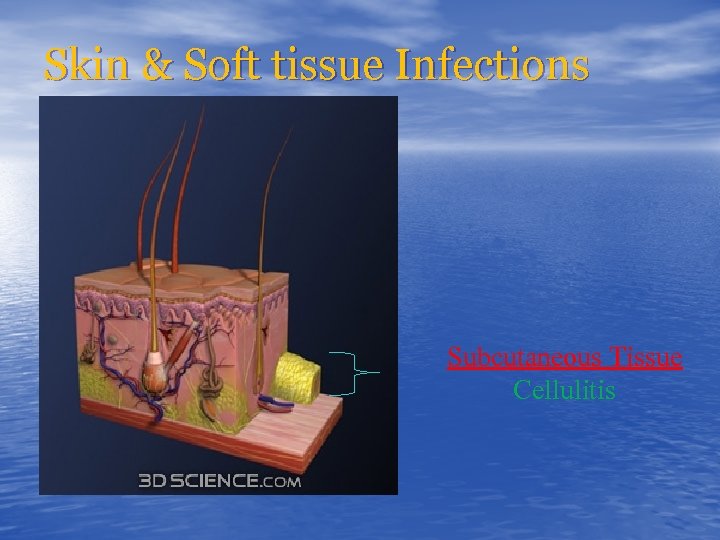

Skin & Soft tissue Infections Subcutaneous Tissue Cellulitis

Skin & Soft tissue Infections Subcutaneous Tissue Cellulitis